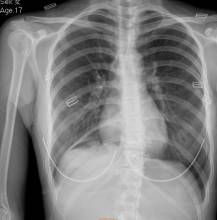

1.X線鋇餐檢查顯示胃大彎有壓跡或有向胃腔內突出的圓形腫物致使幽門變形狹窄。極少數與胃腔相通的雙胃,可見鋇餐流入雙胃腔內。